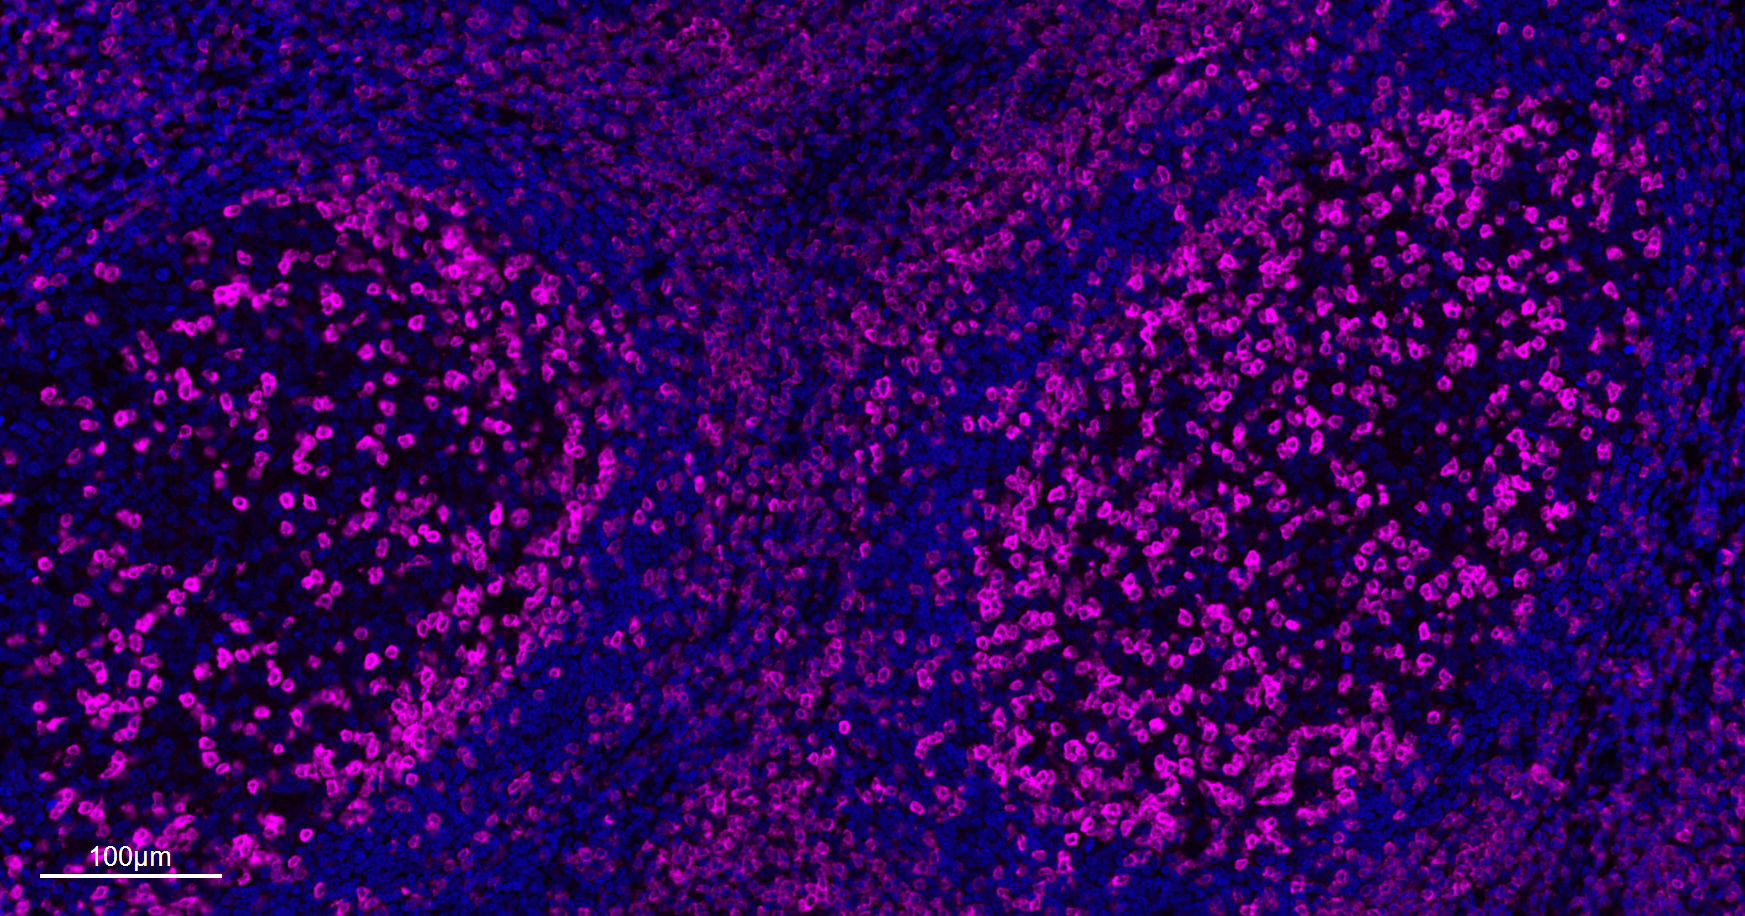

| IF |

1:200-1000 |